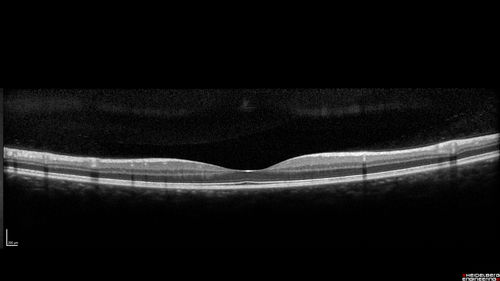

Cat Scratch - Neuroretinitis OD AND retinitis OS - Bartonella henselae positive

27 year old female with exposure to cats and prior fever.  Reports with recent vision loss right eye.  She was treated with doxycycline and within 2 weeks the right eye looks better.  Then she skipped all follow-up visits.  The right eye presented 20/200 and the left 20/16